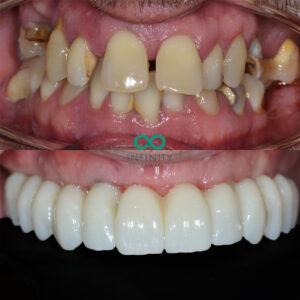

This patient attended our clinic wanting to pursue treatment to replace his failing and missing upper teeth. He was aware of the deteriorating problem over many years however, he was ‘hanging’ onto his teeth due to the fear of being without teeth. The fear of having to spend any time without teeth whilst undergoing treatment to replace teeth is somthing that often puts patient’s off undergoing the treatment they so dearly need.

After a thorough assessment we planned a treatment process whereby this patient would never be without fixed teeth. Our CBCT assessment and 3-Dimensional simultations enabled us to predictably design and manufacture replacement teeth that would fit ‘perfectly’ into his mouth and conform to his ‘style’.

On the same day that he had his teeth removed, we placed bone grafts, gum grafts, dental implants and fitted the replacement teeth. All in the same day!

Following this day of treatment he already had a life changing smile. Over the following 6 months his bone and gum grafts continued to heal and then we simply replaced his ‘initial’ teeth with his ‘final’ teeth. the final teeth are a further improvement to his initial teeth, designed to be even more customised to ensure they stand the test of time.

This patient was able to undergo treatment that he so dearly needed without ever having to be without any of his teeth – truly life changing!